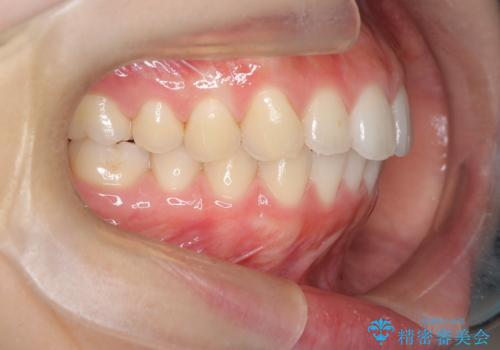

下顎前歯の叢生を短期間で改善

- 患者様は、下顎前歯のガタガタ(叢生)の改善を希望して来院されました。診断の結果、非抜歯で治療可能であると判断し、透明で目立たないインビザラインを使用する矯正治療計画を立案しました。短期間での治療を希望されていたため、IPR(歯間削合)を併用してスペースを確保しながら、効率的に歯を並べることを目指しました。

治療では、インビザラインを用いて計画的に歯を移動させ、短期間での歯列改善を実現しました。IPRを行うことで、抜歯をせずに必要なスペースを確保し、歯列全体を整えました。治療中は、装置の適切な装着時間を守ることが重要であり、患者様にも継続的な協力をお願いしました。また、歯肉や歯根への負担を最小限に抑えるため、歯の移動を慎重に管理しました。結果として、短期間で下顎前歯の叢生を改善し、自然な見た目と機能性を兼ね備えた歯列を実現できました。